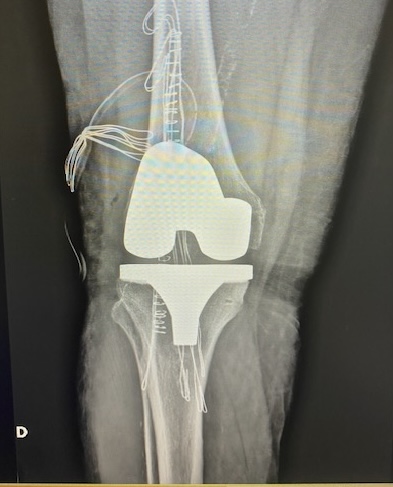

PRÓTESIS DE CADERA Y RODILLA:

Cuando el daño articular es tan importante (artrosis) que ya no responde a tratamiento conservador, está indicado realizar un reemplazo articular con IMPLANTES que recuperen la función articular y eliminen el dolor. Se trata de tratamientos DEFINITIVOS.

Estas cirugías precisan ingreso hospitalario de unos 5 días y la recuperación va desde 6 semanas hasta 3-4 meses.

Prótesis total de rodilla